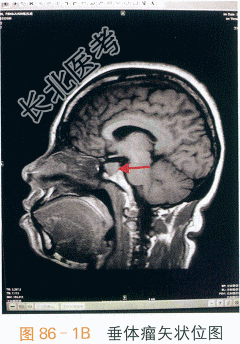

- [材料题] 患者,女性,50岁,因“手足进行性肥大10年余,咽部哽噎感1年半”入院。患者10年前无明显诱因出现双手中指指间关节肿大伴屈曲疼痛,腰痛明显,无发热、晨僵、口腔溃疡及光过敏现象,遂于当地医院就诊,行风湿免疫学检查未见异常(具体报告未见),未予治疗。7年前出现双手指间关节及双足掌趾关节增大、增粗,伴双手、双足增大、肥厚,呈进行性加重(1年内鞋码由36增大至39码),自觉多汗、怕热、易倦,无头疼,无视物模糊及视野缺如,无泌乳,无多尿、多饮、多食,无消瘦,无胸闷、胸痛,多次于当地医院就诊,3次查风湿免疫指标未见异常(具体报告未见),未予处理。查血尿酸水平,未见异常(具体报告未见)。1年半前无明显诱因出现咽部哽噎感,自觉上腭饱满、唇舌增厚、吐字不清,伴呼吸不畅,睡眠时症状明显,但可平卧入睡,偶有夜间憋醒,坐位后缓解,情绪激动时偶有胸闷,持续2~3min后自行缓解,无心悸、胸痛、头痛,无吞咽困难、饮水呛咳,无嗜睡,反复就诊于当地耳鼻喉医院,诊断为“鼻窦炎”,给予曲安奈德喷雾剂、头孢氨苄等治疗后,咽部哽噎感无好转。于五官科医院行鼻窦轴位CT平扫。十冠状位重建示:右侧前组筛窦、上颌窦慢性炎症,鼻中隔偏曲,右侧鼻腔低密度软组织影。1年半以前于五官科医院行喉镜检查未见明显异常。1年前再次于五官科医院行喉镜检查示:披裂间区右侧稍突起,左扁桃体囊肿样物。1个月前于我院耳鼻喉科就诊,行咽喉部平扫示:双侧颈部多发结节影,建议行增强CT检查,遂于半个月前行咽喉部增强CT检查示:颈部淋巴结稍大;左侧甲状腺低密度灶;右上颌窦炎。耳鼻喉科医生建议内分泌科就诊,2天前至我院内分泌科就诊,查甲状腺激素水平正常,生长激素:16.8ng/ml,垂体MRI示垂体右侧结节。甲状腺B超检查示:甲状腺多发占位,考虑增生结节;甲状腺弥漫性病变。现为求进一步治疗以“肢端肥大症”收入我科。抽烟史10余年,每日约10支,已戒烟5年,否认饮酒史。育有1女。43岁前月经规律,经量偏多,43岁起出现经期延长,遂于妇产科就诊,查出子宫肌瘤,遂行子宫切除术,术后无月经。体格检查:T37℃,P90次/min,R20次/min,BP140mmHg/90mmHg,Wt68.5kg,Ht162cm。BMI26.10kg/m²,腰围82cm,臀围100cm,腰臀比0.82。神志清晰,全身皮肤无黄染,腹部见一长约10cm手术瘢痕,手指、足趾粗大,手掌及足背宽厚,手指间关节粗大,无肝掌、蜘蛛痣。右侧腹股沟浅表淋巴结可触及一枚肿大约1cm淋巴结,质韧,无压痛。颧骨及下颌骨突出,牙齿稀疏,唇舌厚,眼球无突出。颈软,气管居中,甲状腺未及明显肿大。胸廓无畸形,双肺查体(-)。心前区无隆起,心界不大,HR90次/min,律齐。腹部查体(-)。四肢脊柱无畸形,活动自如,神经系统检查(-)。双下肢无水肿。实验室和影像学检查:我院2次测定的生长激素(GH)水平分别为9.2ng/ml和16.8ng/ml,口服葡萄糖抑制试验示生长激素升高未被抑制(表86-1);肝肾功能及血脂、肌酶:正常;甲状腺激素水平及相关抗体正常;性激素提示绝经期改变,泌乳素正常;肿瘤、心肌标志物均在正常范围;ACTH-皮质醇节律:正常。胸部X线片检查示:两肺未见实质性病变。垂体MRI平扫示:垂体右侧结节(见图86-1)。垂体MRI平扫十增强示:垂体(右叶11mm×8mm)瘤。胸腹部B超检查示:肝脂肪浸润;胆囊胆固醇结晶;甲状腺弥漫性病变,甲状腺双侧叶结节,部分伴钙化,随访;双侧腹股沟淋巴结。经阴道及腹部超声检查示:盆腔未见占位。咽喉部增强CT检查示:颈部淋巴结稍大,左侧甲状腺低密度灶,右上颌窦炎。心超示检查:左房增大伴左室舒张功能减退。肠镜检查:未见明显异常。骨密度检查:正常。膝关节检查:符合退行性改变。患者入院后完善相关检查,行口服葡萄糖抑制试验示生长激素升高未被抑制,垂体MRI示垂体右叶占位。